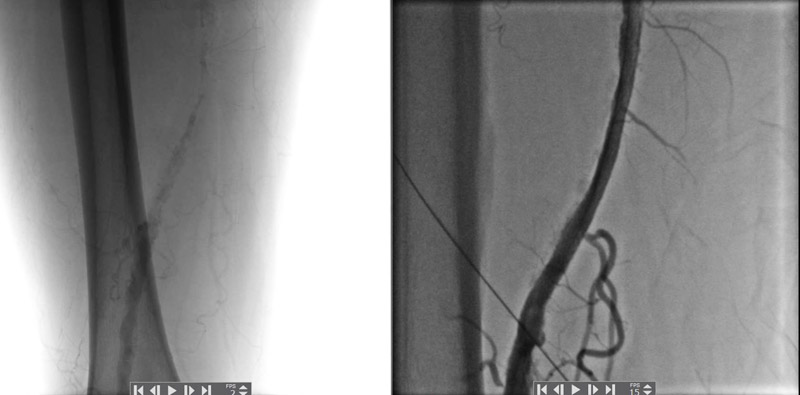

Arterial rekonstruksiyaların nəticələri